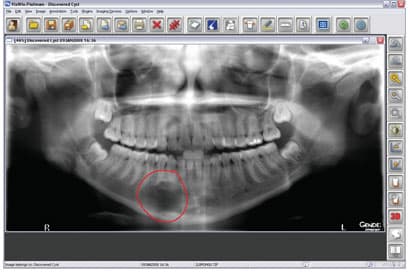

Digital Imaging—Life-Changing Technology

Digital imaging is part of efficient communication, and it adds to the “wow factor.” Patients may see their teeth in the mirror every day, but we must supply images that will let them learn about improving their dentition. For this, digital radiography has become the standard of care in diagnostics. This technology provides superior-quality images in a couple of seconds. It is an excellent diagnostic aid with which to compose a treatment plan. On the screen, we can enhance or zoom in, invert or emboss an image to communicate the possibilities in an unobtrusive way. Sometimes a patient may have a problem such as a fractured restoration that cannot

IN THE PAST, DENTAL DAYDREAMERS PONDERED THE ABILITY TO CAPTURE A 3-D IMAGE OF THE MOUTH AND TO VIEW IT FROM ALL ANGLES. The ability to rotate that 3-D mode and zoom in on details was an even greater aspiration. Then, to coordinate all of the information for integration with other applications- such as guided implant placement software-promised to add even more value to the technology. All of these benefits are not just relegated to the dental visionaries of the future. 3-D imaging is available, here and now, and is actively improving practices across all dental disciplines. IMPLANTOLOGY Jack T. Krauser, DMD: 3-D radiography has made an astonishing and

2-D imaging (standard film and digital X-rays) has long been the standard for dental scans-despite the somewhat costly price and high radiation dosages. Now 3-D imaging technology is set to address these issues. Cone Beam technology obtains crucial information at much higher resolution using lower radiation, and is cost-effective for practitioners and patients. Indeed, such important benefits will certainly give traditional 2-D X-ray imaging a run for its money. THE INTRODUCTION OF CONE BEAM TECHNOLOGY Here's where 3-D imaging is invaluable. It lets dentists see patients' anatomies in all dimensions by creating a 360° analysis. These images give dental professionals a complete makeup of the human jaw, face, and